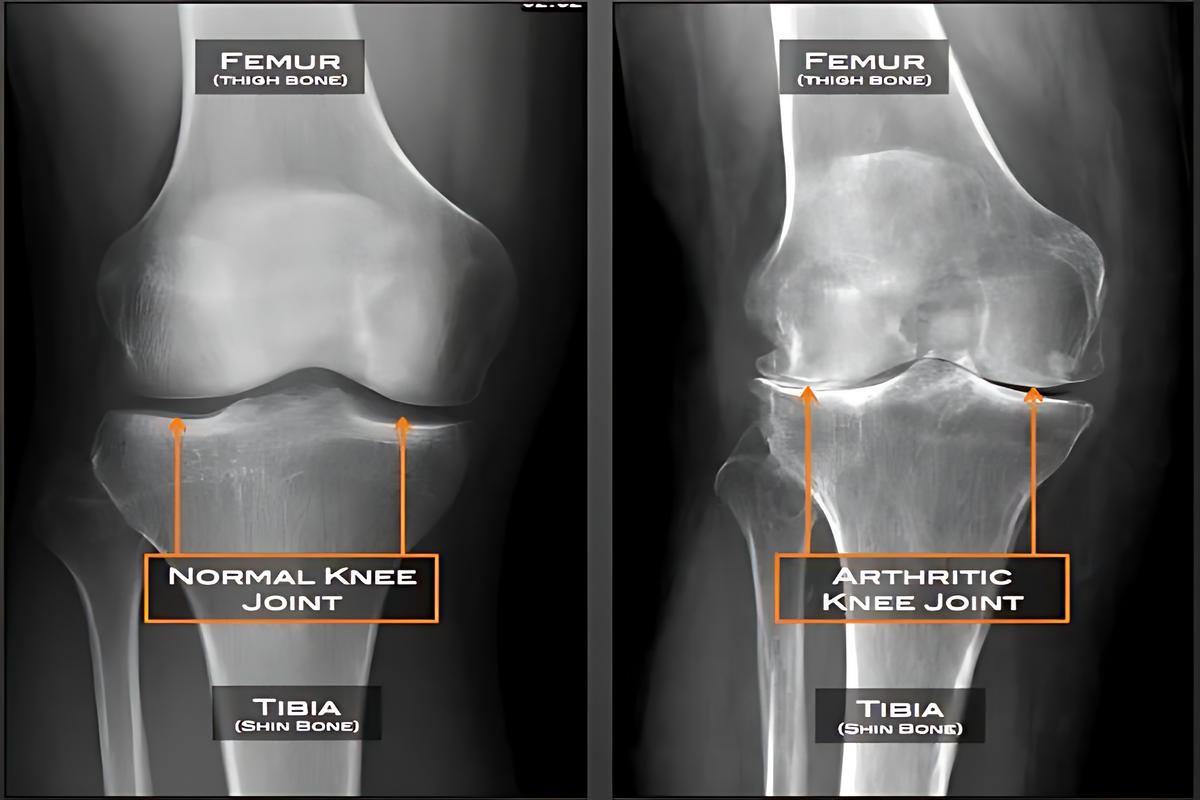

Η αρθρίτιδα είναι μία εκφυλιστική και συχνά φλεγμονώδης πάθηση της άρθρωσης, κατά την οποία καταστρέφεται σταδιακά ο αρθρικός χόνδρος. Η απώλεια του χόνδρου οδηγεί σε άμεση τριβή των οστών μεταξύ τους, προκαλώντας πόνο, δυσκαμψία και, σε προχωρημένα στάδια, παραμόρφωση της άρθρωσης.

Το πιο συχνό σύμπτωμα είναι ο πόνος στο γόνατο, ιδιαίτερα κατά την κίνηση ή τη φόρτιση. Πολλοί ασθενείς αναφέρουν δυσκαμψία μετά από ξεκούραση ή τις πρωινές ώρες, καθώς και οίδημα της άρθρωσης.

Κατά την κίνηση μπορεί να ακούγεται ή να γίνεται αισθητό «τρίξιμο», ενώ στα προχωρημένα στάδια εμφανίζεται παραμόρφωση του γόνατος και σημαντικός περιορισμός της κινητικότητας.